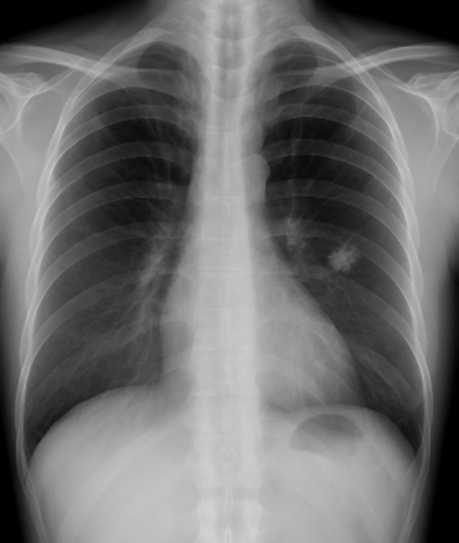

一般撮影とは

一般撮影は放射線を使用して体内の骨や臓器を撮影する検査で、いわゆる「レントゲン検査」と言われています。

当クリニックでは最新のデジタルX線装置を導入しており、従来よりも被ばくを抑えつつ、鮮明な画像を得られます。また、レントゲン室を3部屋備えており、スムーズに検査を受けていただけます。